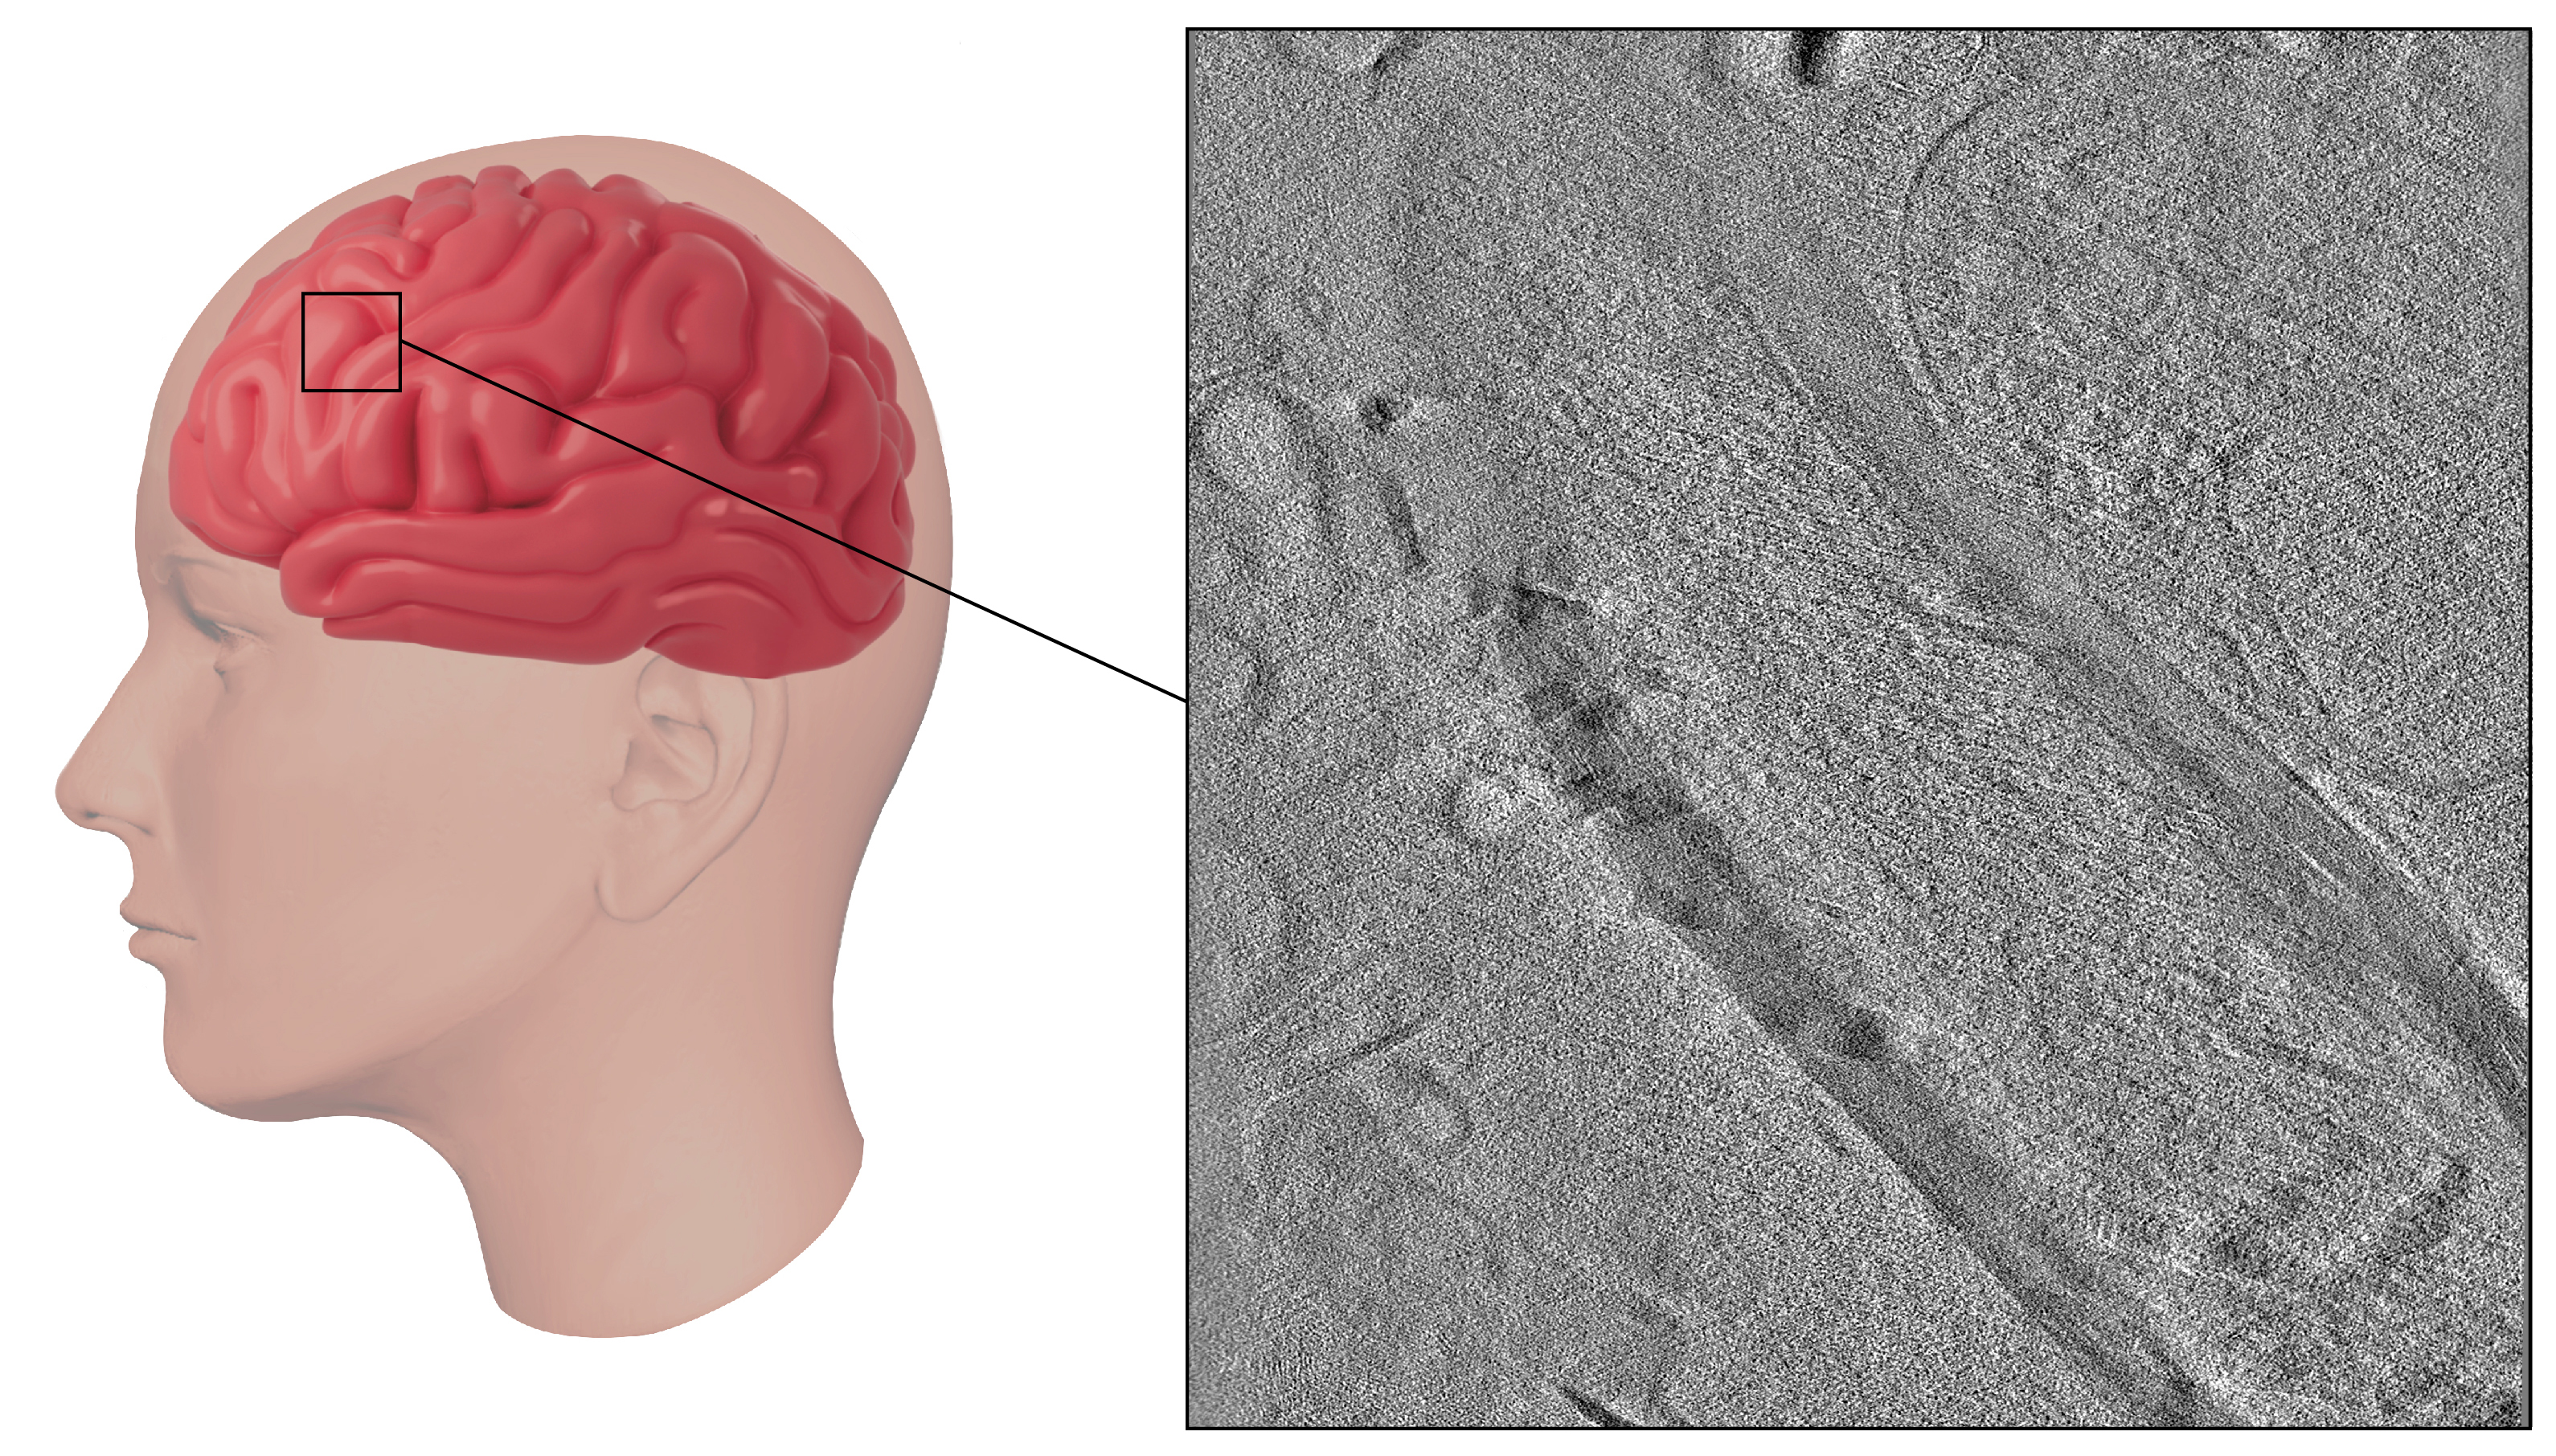

A close-up look at human brain tissue using a new technique developed by Benjamin Creekmore and colleagues.

By applying this approach to brain tissue from individuals with Alzheimer's disease, they were able to observe intact structures within cells, such as tau fibrils, a hallmark of Alzheimer’s disease, and cellular components that try to break down these fibrils. The team also visualized and measured myelin, a sheath that’s critical for nerve function but that breaks down in certain diseases, such as multiple sclerosis.

Creekmore and colleagues obtained brain tissue from autopsies, flash froze it directly on special grids with liquid ethane, and used a powerful tool called a xenon plasma focused ion beam (FIB) to cut thin slices for imaging. This method allowed them to look at the brain tissue in its near-natural state without cutting with a knife blade, adding chemicals, or slower freezing, all of which can lead to changes in the structures.